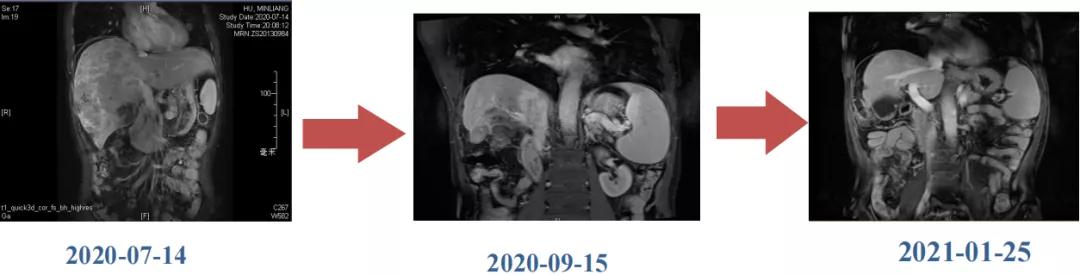

编者按:手术切除是肝癌最有效的治疗手段之一,但多数肝癌患者确诊时已处于晚期无法接受根治性手术。转化治疗已成为中晚期肝癌的重要治疗手段,可以通过局部和或系统治疗(如靶免治疗)将初始不可切除肝癌(uHCC)患者转化为可切除,从而改善患者预后。该病例为一例巨块型肝癌伴门脉癌栓形成合并肺转移,中国肝癌临床分期(CNLC)IIIb期,治疗前肿瘤最大直径18.4cm,通过接受仑伐替尼(乐卫玛®)联合信迪利单抗治疗后肿瘤降期,肝内病灶实现R0切除。患者目前OS已达17个月。

肿瘤学评估(用药后2个月对比6个月):肝内主瘤明显缩小,动脉期强化降低;子灶消失;门脉右支癌栓明显缩小坏死;肺转移灶缩小,大部分消失。

Δ治疗过程中病灶影像学变化

用药6个月后:肝脏病灶明显缩小,子灶消失,仅有少量动脉期强化;肺转移单个持续缩小稳定,PET CT活性弱;HBV DNA 转阴;可考虑转化切除。